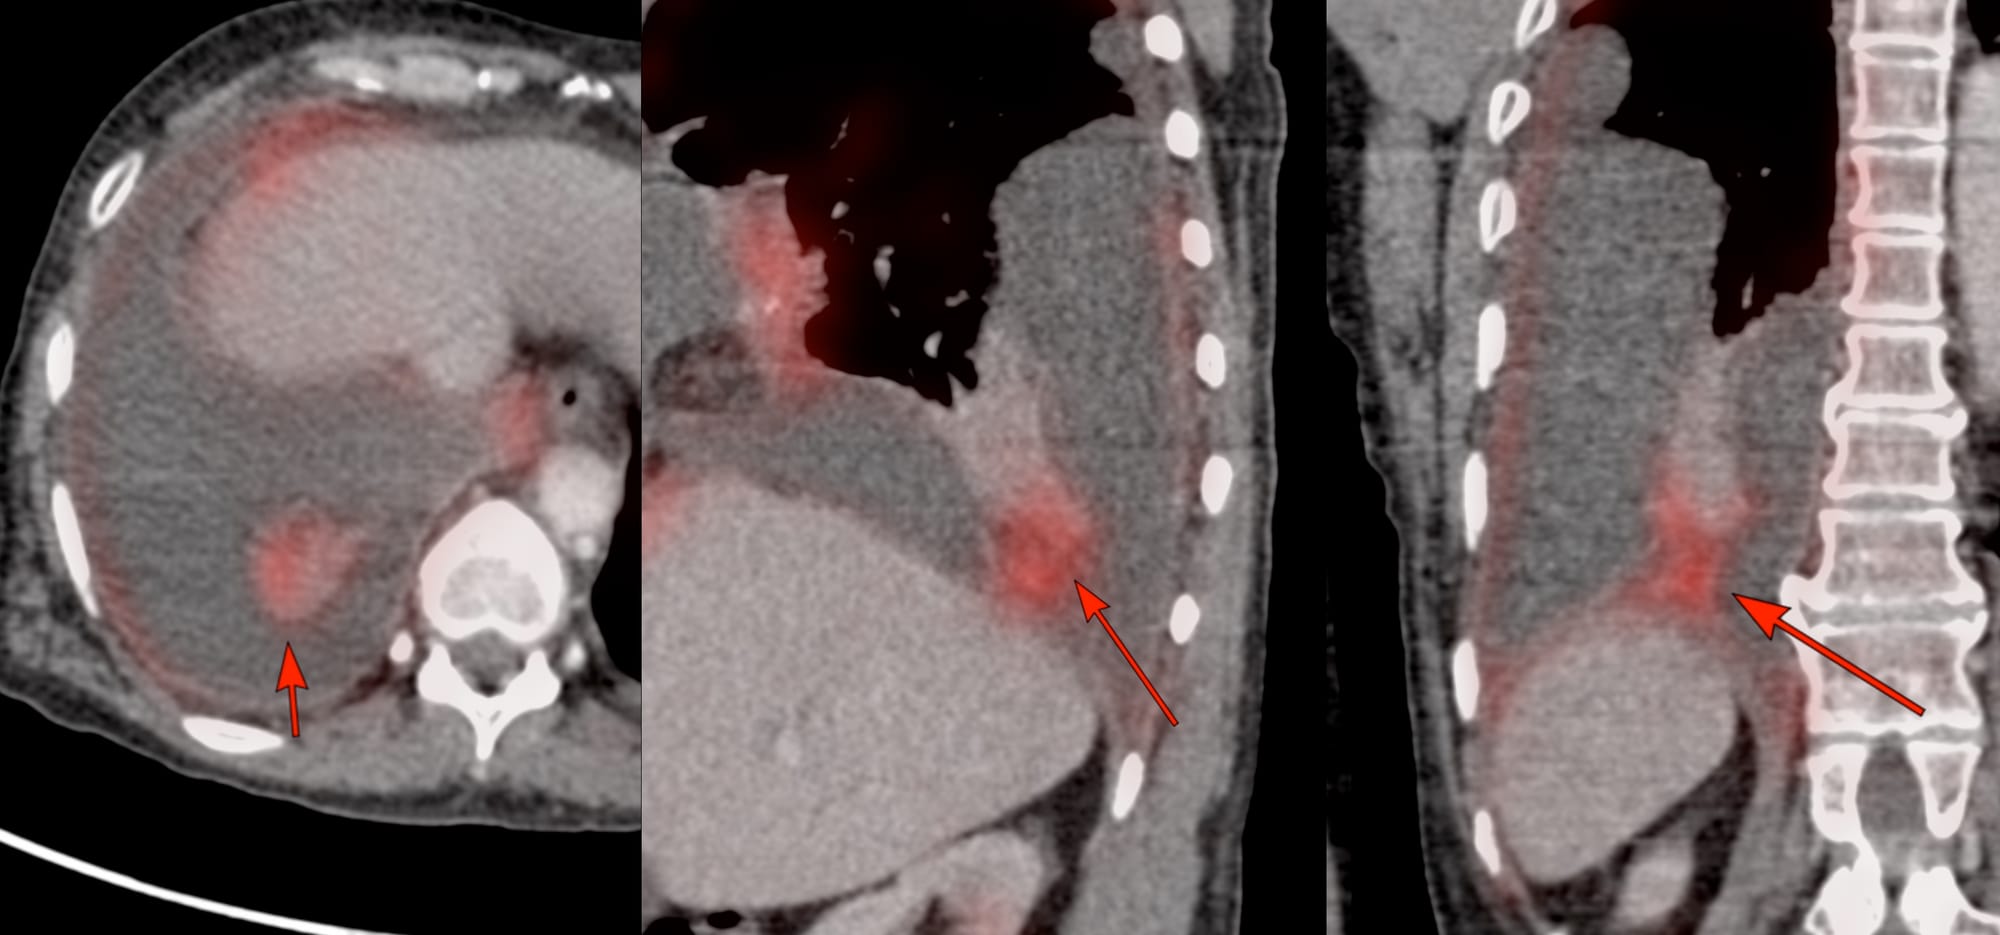

PET/CT showed a focal lesion arising from the posterior basal segment of the right lower lobe attached to the visceral pleura (arrows in Fig 1).